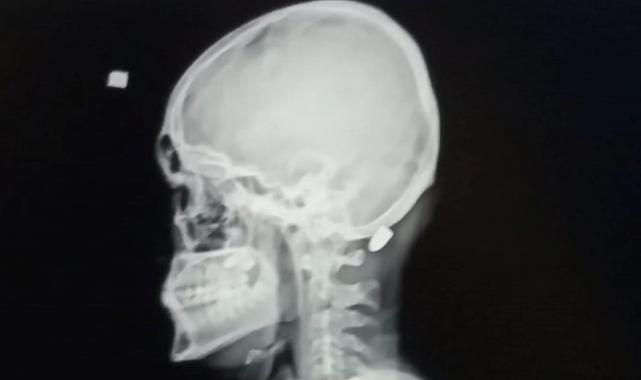

Kentte yetkililerin tüm uyarılarına rağmen yorgun mermi vakalarının arkası kesilmiyor. Yorgun mermi vakalarında kimileri hayatını kaybediyor, kimileri yaralanıyor, kimileri de sakat kalma tehlikesi ile karşı karşıya kalıyor. Trabzon’un Ortahisar ilçesinde 9 Nisan 2016 tarihinde Mustafa Mandıralı (22) isimli inşt işçisi işe giderken otobüs durağı yakınında nereden ve kim tarafından atıldığı belli olmayan ve "Yorgun mermi" diye tabir edilen merminin hedefi oldu. Merminin başına isabet etmesi sonucu Mandıralı ağır yaralandı.